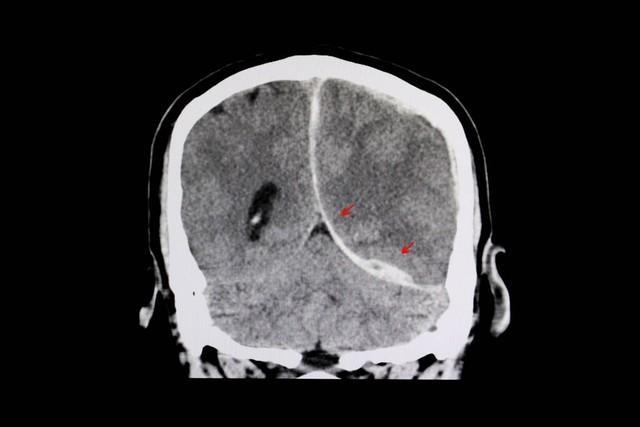

腦出血在醫學上被稱爲出血性中風,也稱爲腦溢血。高血壓患者由於其不穩定的血壓問題,使得自身的的血管長期處於高壓狀態,從而加速了自身血管的老化進程,使自身血管的血管壁變得更加脆弱,容易破裂。

​當血壓突然升高時,特別是收縮壓急劇升高時,血管壁上的壓力就會迅速增加,當壓力過大時,就可能會導致腦出血的問題發生。此時,血液就會從破裂的血管中流出,進而壓迫腦組織,對腦組織造成損傷,甚至還會威脅生命健康。